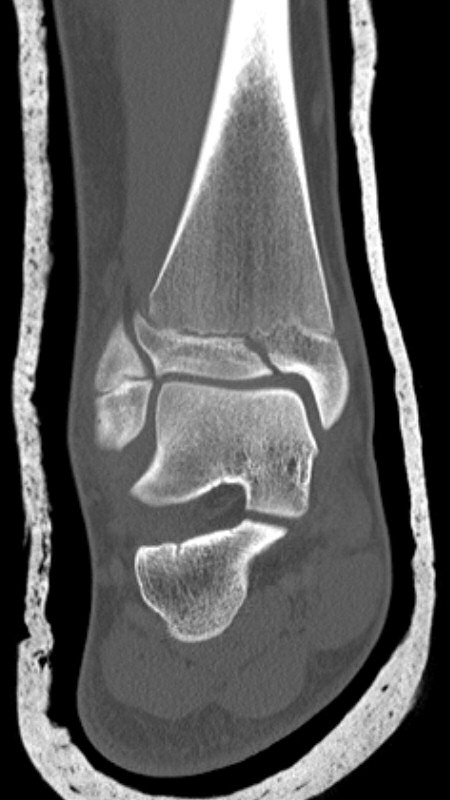

Distal tibiafyseolys SH 4 triplansfraktur (barn)

Triplanfraktur = triplansfraktur = treplansfraktur: fraktur i distala tibia som engagerar både metafys, fys och epifys. Kan vara 2, 3 eller 4 fragment. I 50 % av fallen är även fibula frakturerad [3].

Exempel på triplansfraktur hos nästan färdigvuxet barn

På akutmottagning

Gör DT för att avgöra frakturtyp och felställning.